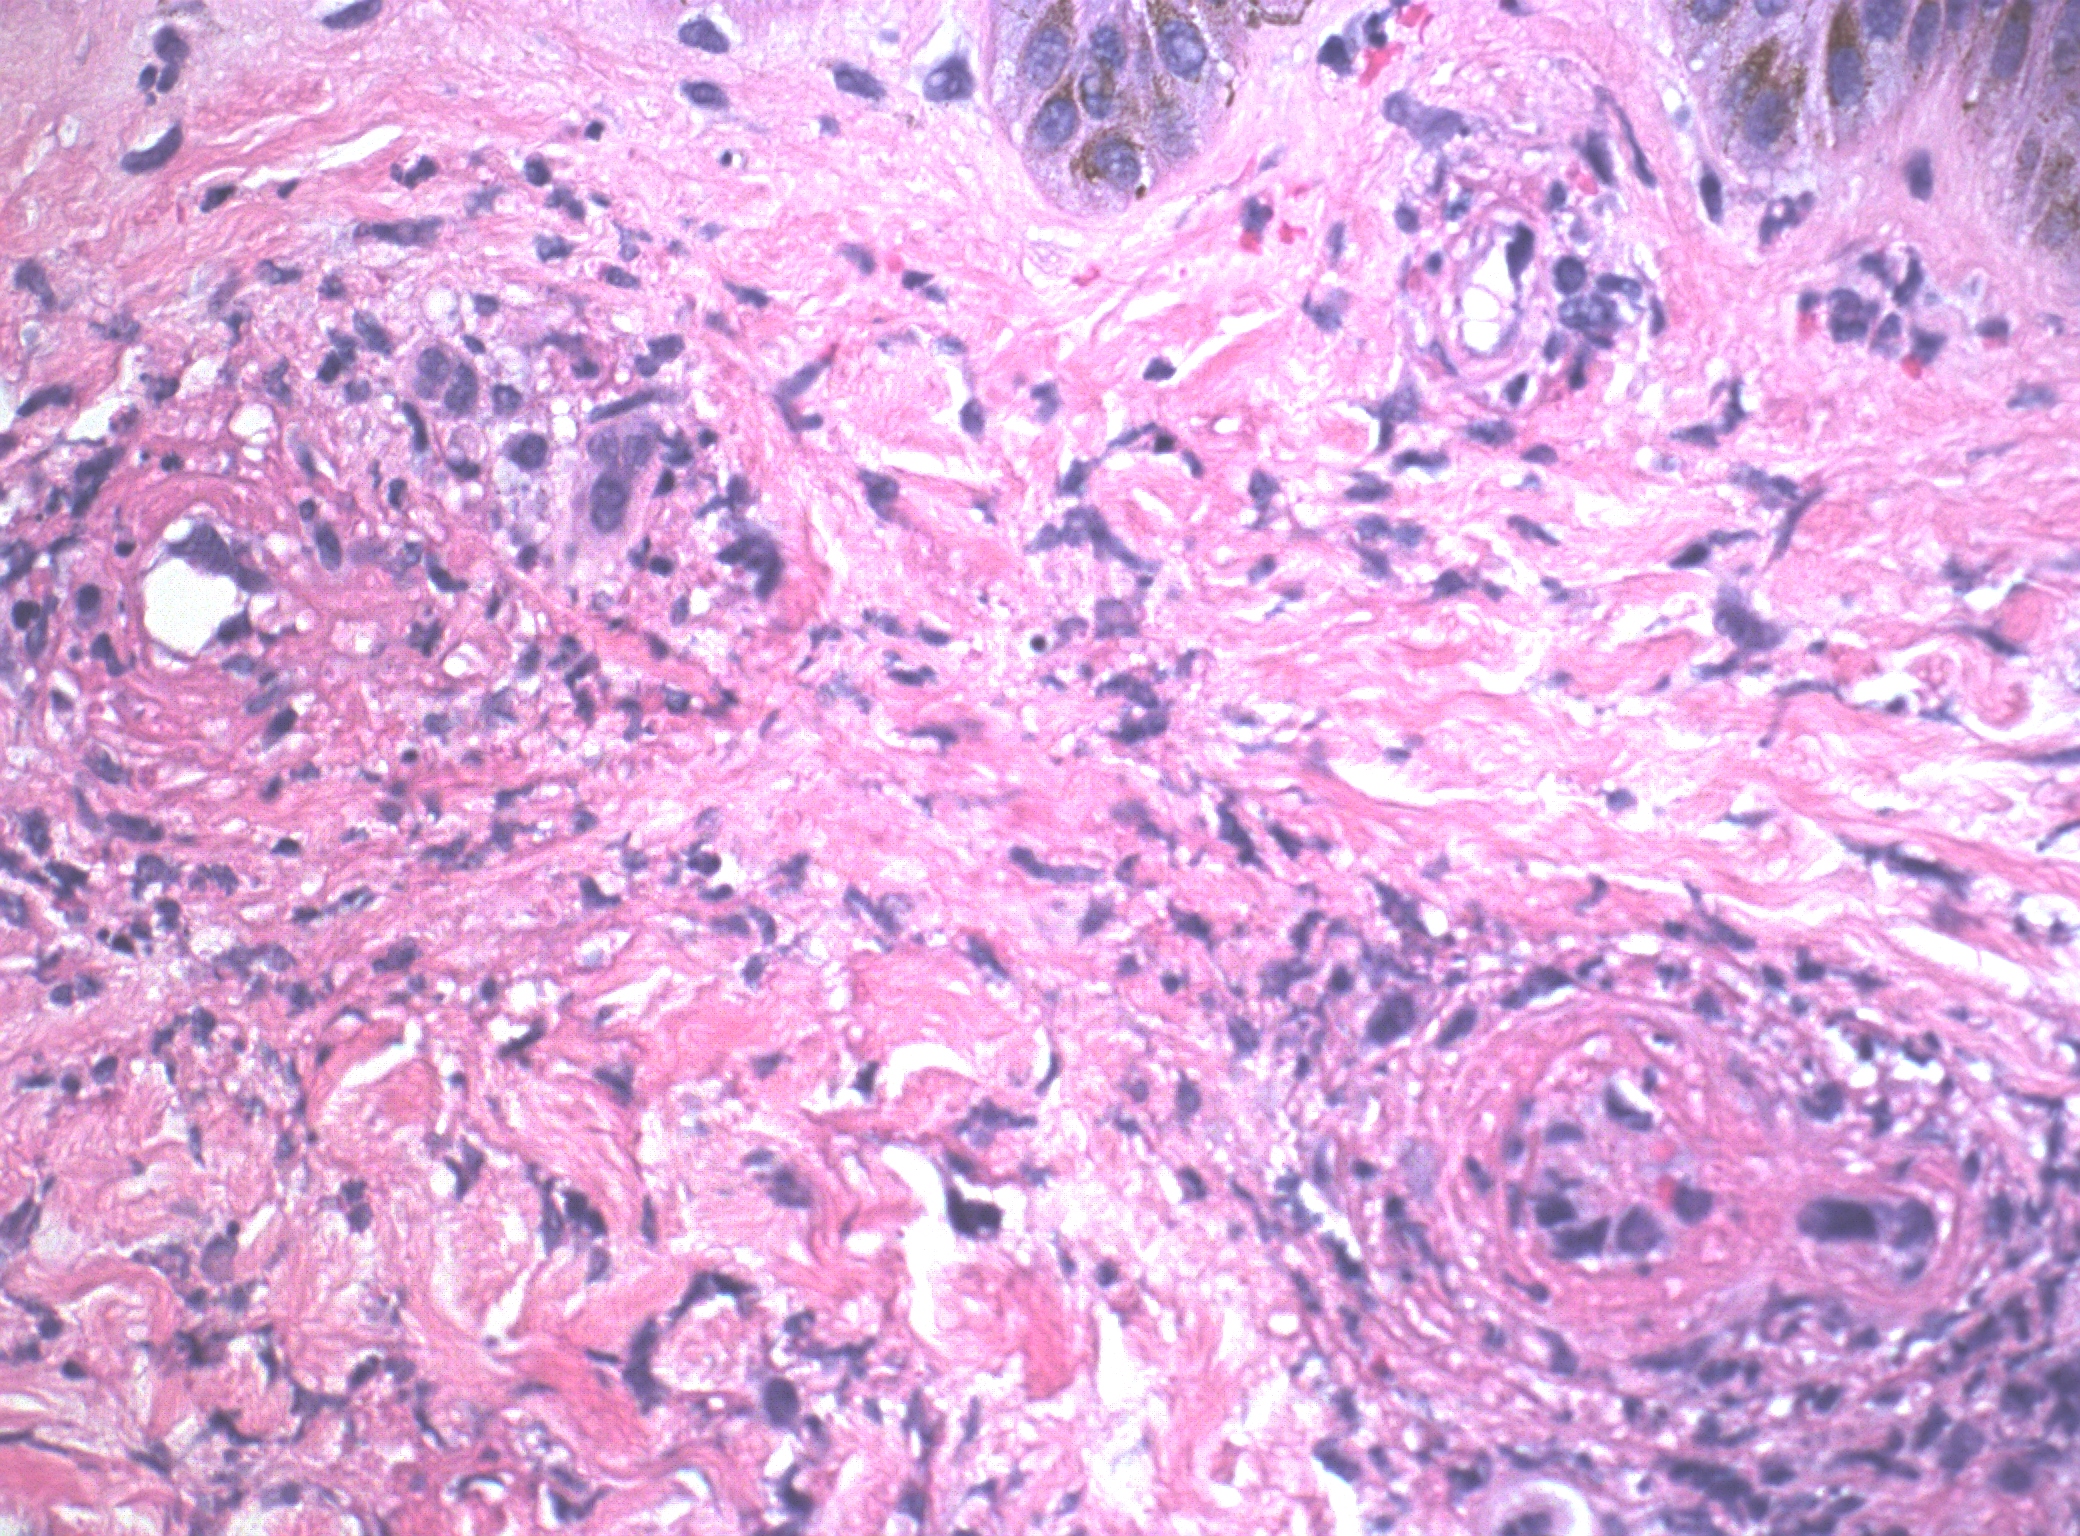

Case Presentation: A 51-year-old female with no past medical history presented with a rash that developed a week ago which started on her right calf and then progressed all over her body. She was on ibuprofen for right knee pain for the 3 weeks before her presentation. Vital signs were normal. Laboratory tests revealed leukocytosis, and elevated inflammatory markers [(erythrocyte sedimentation rate (112 mm/hr), and C-reactive protein (10.54 mg/dL)]. Antinuclear antibodies and qualitative cryoglobulin C returned positive and serum complement protein C3 was elevated (245 mg/dl). Rheumatoid factor, CCP antibodies IGG/IGC, Sjogren’s antibody (anti-SS-A/-SS-B), anti-DNA(DS), serum complement C4, ANCA profile (anti-MPO antibodies, anti-PR3 antibodies, atypical P ANCA) were negative. Thyroid stimulating hormone, creatinine, liver enzymes, prothrombin time, and partial thromboplastin time were normal. Urine analysis showed no proteinuria. Human immunodeficiency virus antibody/antigen test, hepatitis B and C serologies, syphilis screening, and Lyme serology were also negative. The rash evolved from maculopapular purpuric lesions to the development of tender vesicles, bullae, and ulcerations therefore a punch biopsy of the skin was performed, which showed leukocytoclastic vasculitis. Ibuprofen was stopped and the patient was started on a prednisone taper. The eruptions cleared and bullae started healing. The patient was diagnosed with biopsy-proven leukocytoclastic vasculitis with cryoglobulinemia secondary to ibuprofen use. She was discharged on oral prednisone, and topical triamcinolone, and referred to dermatology, and rheumatology, for further evaluation. She reported improvement at her follow-up appointment in the dermatology clinic.

Discussion: This case highlights the importance of considering medication-induced leukocytoclastic vasculitis when evaluating patients who present with unexplained rash. Ibuprofen-induced leukocytoclastic vasculitis is a rare but recognized adverse reaction to ibuprofen involving the drug acting as a hapten and initiating immune complex deposition and activation of the complement cascade in postcapillary venules, resulting in fibrinoid necrosis. Drug-induced eruptions are based on inferential evidence, usually involving a history of ingesting the suspected drug and resolution of the eruption once the drug is discontinued [1]. Diagnosis is dependent on skin biopsy but also relies on a combination of clinical features and exclusion of other causes [2].